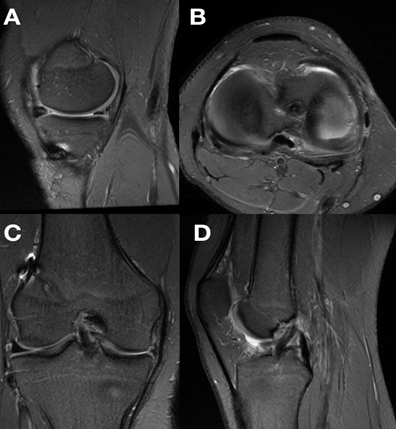

Consulta en el servicio de ortopedia infantil presentando al examen físico inestabilidad anterior dada por el test de Lachman positivo. Concomitantemente presentaba dolor a nivel de la interlínea interna, siendo positivas las pruebas de McMurray y Apley en relación al menisco interno. Se solicitaron radiografías anteroposterior (AP) y perfil (P) de la rodilla lesionada en busca de otras lesiones, siendo estas normales. Se solicitó una resonancia nuclear magnética (RNM) de la rodilla derecha, evidenciándose la rotura de LCA y una lesión longitudinal del cuerno posterior del menisco interno (Figura 1). Se coordina para cirugía artroscópica con el planteo de realizar una reconstrucción transfisaria del LCA y una reparación inside - out del menisco interno, al año de producida la lesión. Se realizaron en este momento los scores de Tegner & Lysholm, además del IKDC previos a la cirugía (Tabla 1 y 2).

Figura 1. RNM de rodilla derecha de paciente adolescente de 14años. A. Corte sagital en T2 que muestra (flecha negra con borde blanco) la ausencia de LCA. B y C. Corte sagital y axial en T2 que a su vez hace notar una lesión longitudinal periférica del cuerno posterior a nivel de la zona roja - roja del menisco interno (flecha blanca con borde negro).

Se proscribió el apoyo por 6 semanas, y se comenzó con tratamiento fisioterápico precoz. Se volvieron a realizar los scores IKDC, Tegner & Lysholm a los 3 y 6 meses, al año y a los 2 años posterior a la cirugía (Tabla 3). Además a los 6 meses, se solicitó una nueva RNM para control imagenológico de la reconstrucción del LCA y de la reparación meniscal (Figura 4). A los dos años del seguimiento clínico, se solicitó una goniometría de miembros inferiores para descartar desaxaciones o dismetrías debidas a una lesión fisaria (Figura 5). No se evidenciaron complicaciones de la herida, ni re-rotura del LCA, ni falla de la sutura meniscal, ni artrofibrosis de dicha rodilla.

Figura 4. RNM de rodilla derecha a los 6 meses. A y B. Corte sagital y axial en T2 que muestra el resultado de la reparación meniscal inside-out.C y D. Corte coronal y sagital en T2 que muestra la reconstrucción del LCA con pata de ganso.